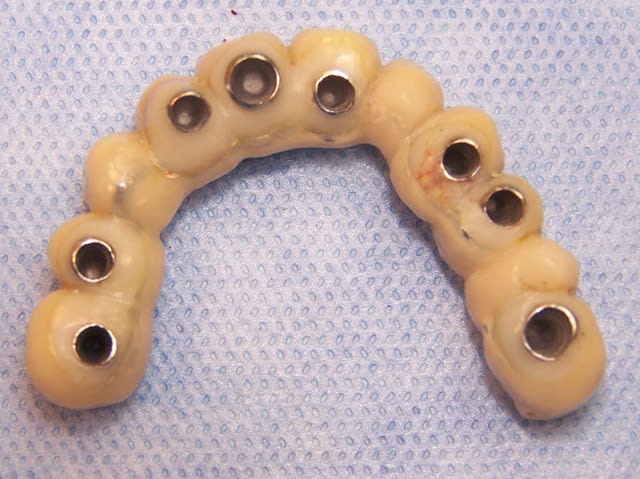

Eu pratiquant une mise en charge légèrement ou différée tu perds tous les avantages de la mise en charge immédiate. Le protocole de mise en charge immédiate POSITDENTAL est maintenant éprouvé, inévitablement il requiert une bonne maîtrise de l’implantologie. La passivité et précision du bridge se faont lors de la mise en place.

Vidéo d'une mise en charge immédiate: